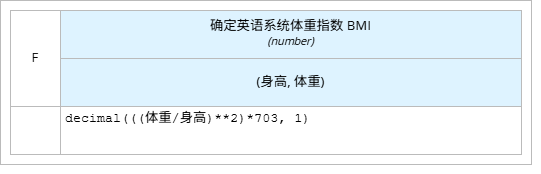

业务知识函数

l “确定英语系统体重指数 BMI”即维基百科定义的体重指数计算公式。它有2个参数即身高、体重。使用文字表达式的盒装结构。